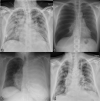

A wide spectrum of conditions, from life-threatening to non-urgent, can manifest with acute dyspnea, thus presenting major challenges for the treating physician when establishing the diagnosis and severity of the underlying disease. Imaging plays a decisive role in the assessment of acute dyspnea of cardiac and/or pulmonary origin. This article presents an overview of the current imaging modalities used to narrow the differential diagnosis in the assessment of acute dyspnea of cardiac or pulmonary origin. The current indications, findings, accuracy, and limits of each imaging modality are reported. Chest radiography is usually the primary imaging modality applied. There is a low radiation dose associated with this method, and it can assess the presence of fluid in the lung or pleura, consolidations, hyperinflation, pneumothorax, as well as heart enlargement. However, its low sensitivity limits the ability of the chest radiograph to accurately identify the causes of acute dyspnea. CT provides more detailed imaging of the cardiorespiratory system, and therefore, better sensitivity and specificity results, but it is accompanied by higher radiation exposure. Ultrasonography has the advantage of using no radiation, and is fast and feasible as a bedside test and appropriate for the assessment of unstable patients. However, patient-specific factors, such as body habitus, may limit its image quality and interpretability. Advances in knowledge This review provides guidance to the appropriate choice of imaging modalities in the diagnosis of patients with dyspnea of cardiac or pulmonary origin.